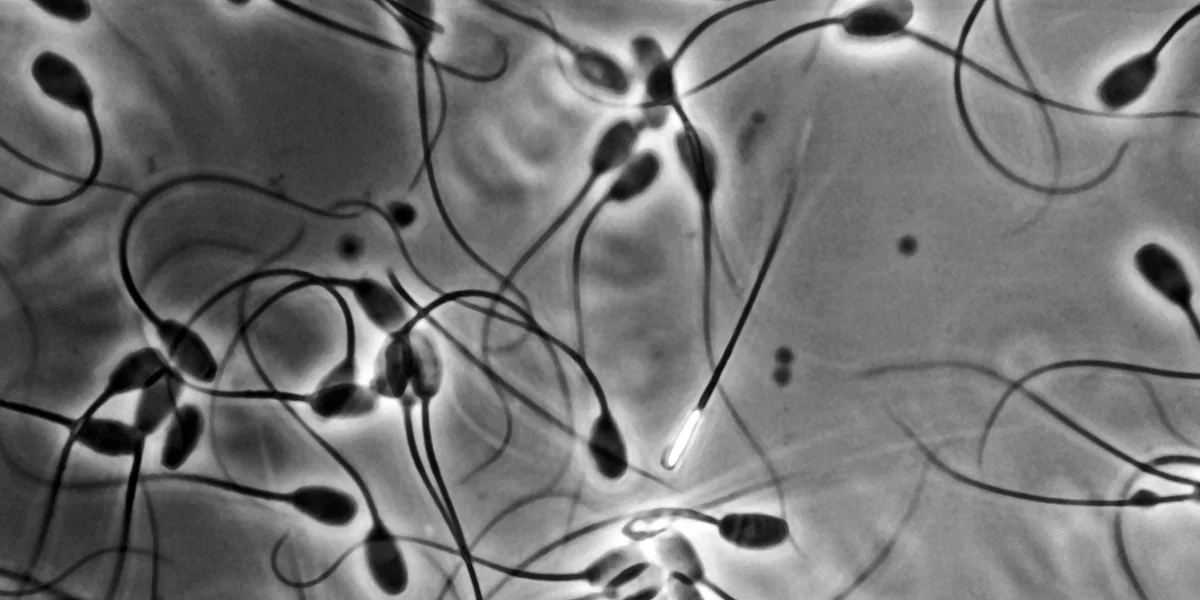

Neben Menschen sind auch Hunde, Pferde und sogar Wildtiere vom Spermienrückgang betroffen Foto: Avalon/imago